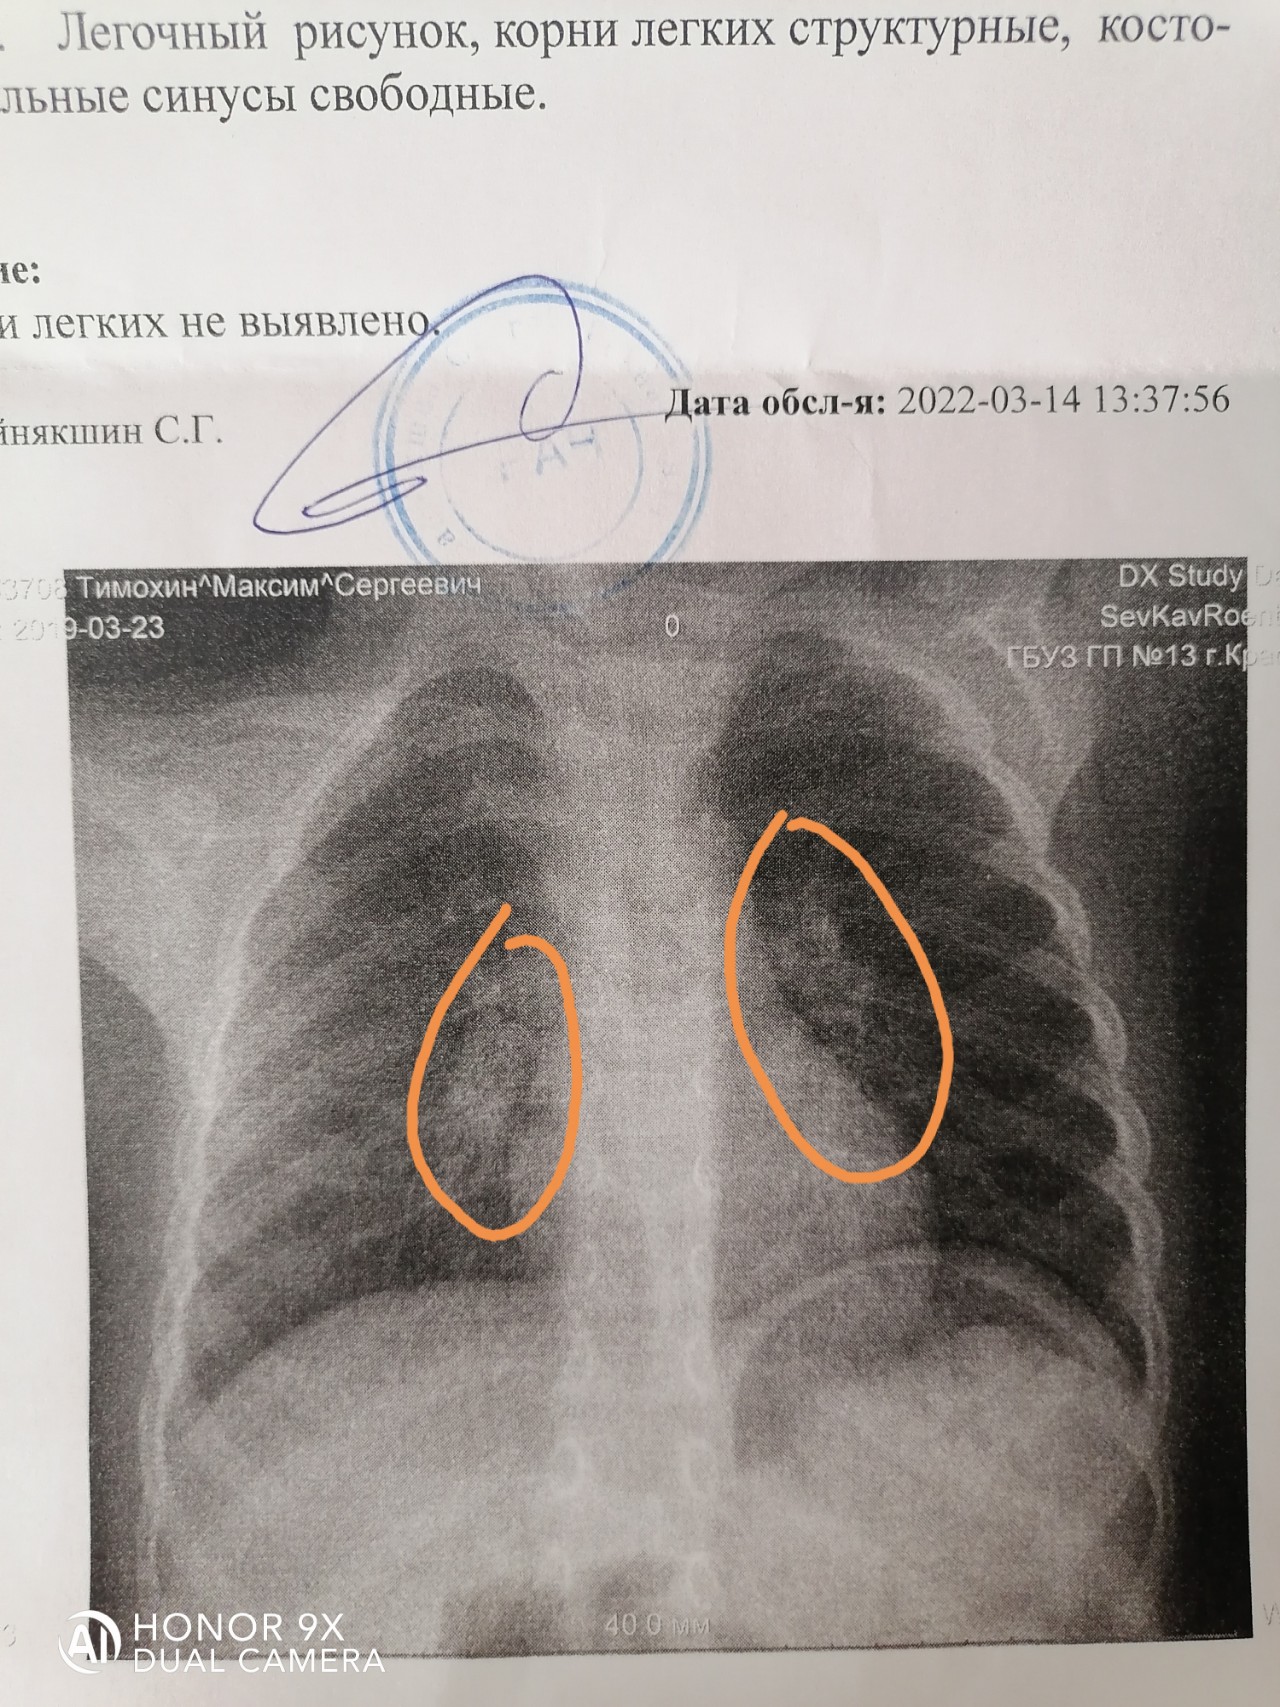

Ячеистая деформация легочного рисунка: медицинская визуализация